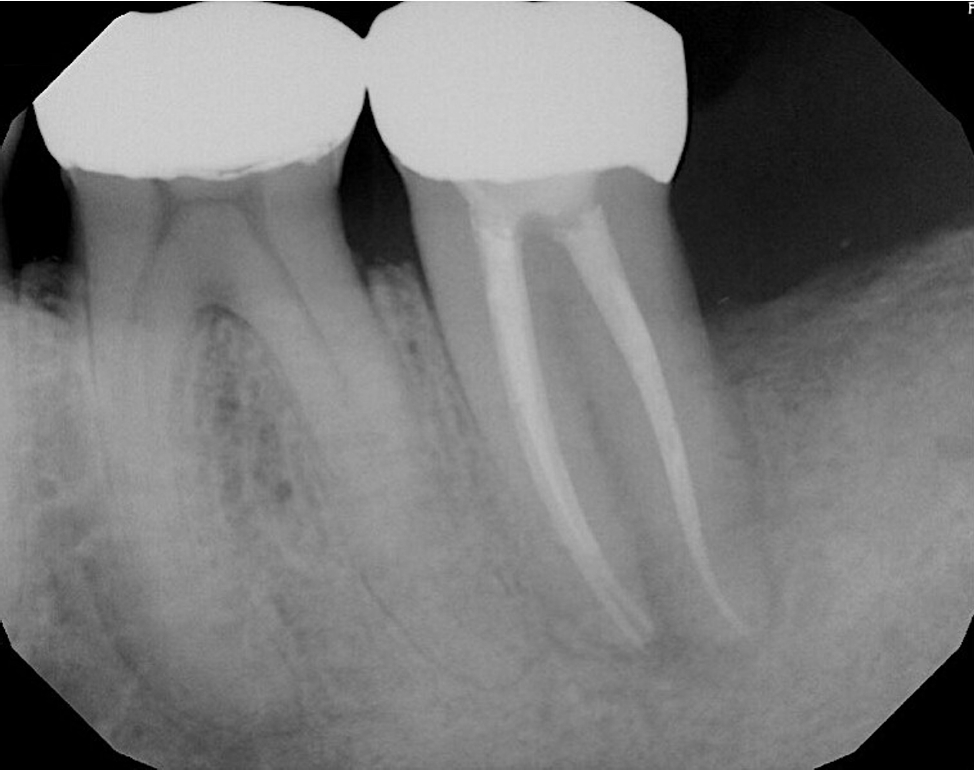

The patient was lost to follow-up until he reported again at 24 months, at which time clinical examination revealed that a full-coverage restoration on tooth #18 had been placed, restoring form and function (Figure 6). Clinical gingival health was noted on a reduced periodontium. Draining sinus tract remained resolved, and probing depths were improved to 3–4 mm. The tooth exhibited no mobility. Periapical radiograph (Figure 7) showed significant resolution of the periapical radiolucency with substantial bone regeneration along the length of the distal root. The patient was greatly appreciative that his natural dentition was conserved, which motivated him to ensure continued dental care maintenance.

Figure 7.

Periapical radiograph showed significant resolution of the periapical radiolucency with substantial bone regeneration along the length of the distal root.

Figure 7. Periapical radiograph showed significant resolution of the periapical radiolucency with substantial bone regeneration along the length of the distal root.